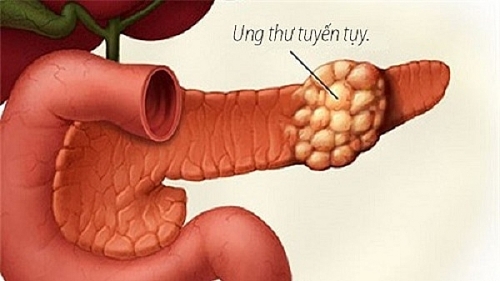

Dấu hiệu nhận biết ung thư tụy

Dấu hiệu nhận biết ung thư tụy, nguyên nhân và cách phòng ngừa căn bệnh này như thế nào? Cùng tìm hiểu về ung thư tụy ngay sau đây: